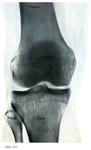

自由下肢の骨

2. 自由下肢骨の結合